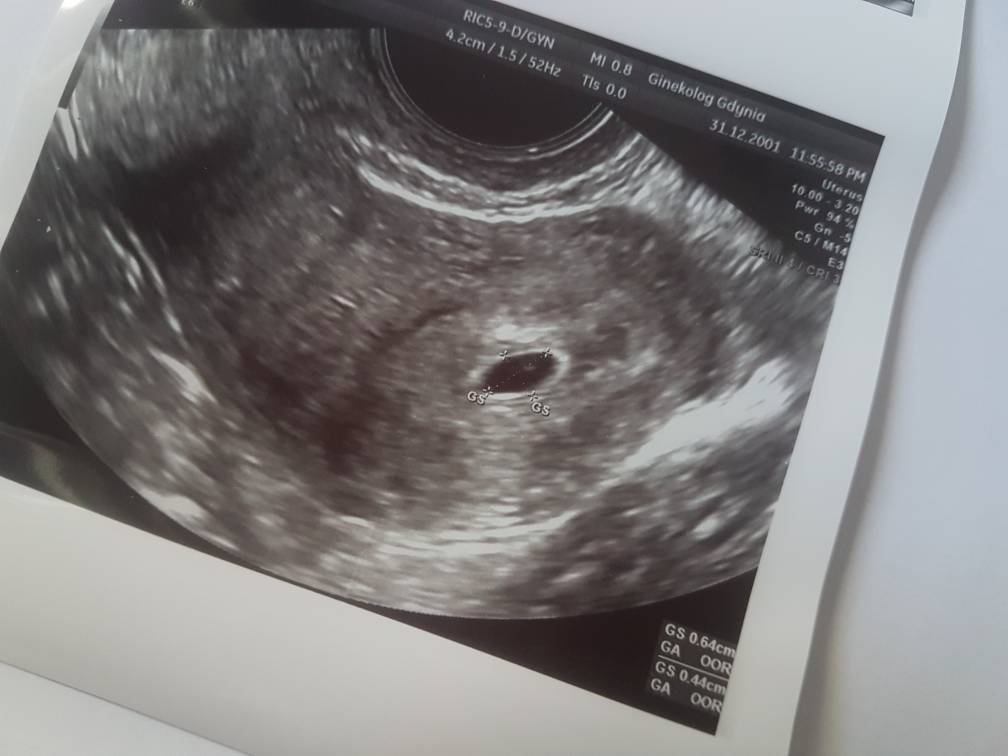

Jestem już po pierwszym usg. Tak dla pewności, ponieważ jestem po poronieniu. Było w czerwcu. I wolałam dmuchać na zimne i dla świętego spokoju pokazać się lekarzowi. Dostałam luteine dopochwowo z racji poronień, lekarz się bał więc w razie czego mam brać. Kazał zrobić betę, jutro/czwartek zobaczyć jak przyrasta i sprawdzić progesteron. Mam brać euthyrox dalej. Ale wynik testosteronu skoczył. Z 1,03 do 2,61. Wyniki tarczycy podobno są dobre ale czekam na swoją zaufaną lekarkę. Jeszcze dziś zadzwonię do niej. Wykupiłam kwas foliowy. Ale nie pamiętam ile mam go brać. Nie brałam wcześniej. Owulacja była z prawego jajnika. Trochę mnie to martwi. Bo cały czas z prawego coś się dzieje. No i na razie jest w porządku. Zobaczymy jak beta. Chciałabym odetchnąć z ulgą ale nie umiem tak się boję [emoji17] O dzidzie. Modlę się, żeby było dobrze wszystko. Zobacz załącznik 890182